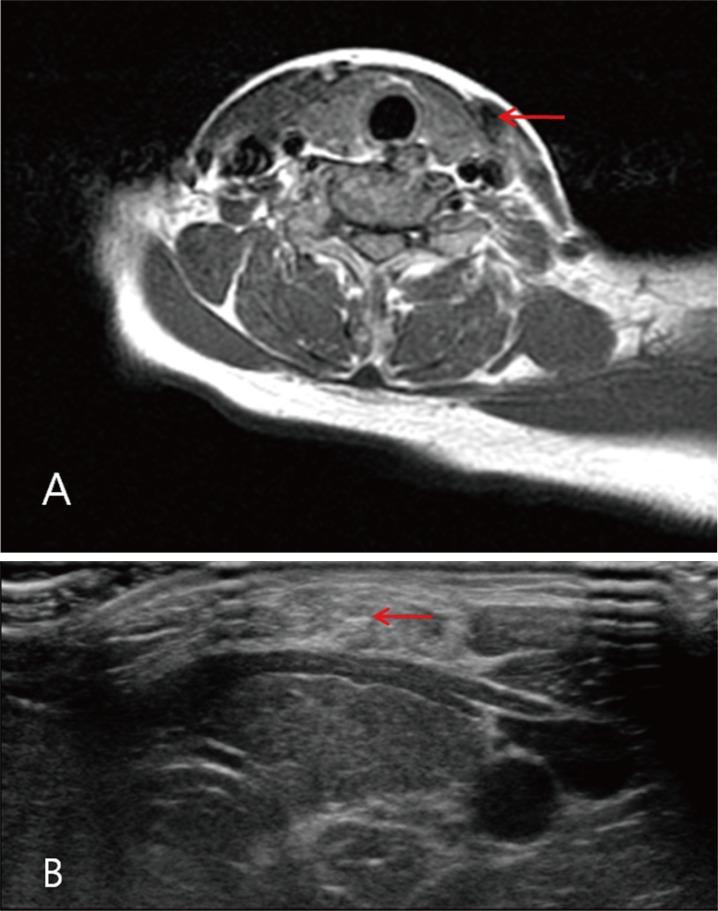

在成人先天性肌性斜颈(CMT)患者中,物理治疗效果不佳,因为胸锁乳突肌(SCM)已发育完全。虽然手术松解可治疗成人CMT患者,但全身麻醉风险和术后可见瘢痕令人担忧,尤其是对症状较轻的患者。在本文中,我们报告了局部麻醉下小切口肌切开术治疗此类患者的经验。对所有接受单纯肌切开术的成年患者进行了回顾。手术适应症为SCM肌肉中纤维化带较轻且肌肉长度差异最小的患者。所有患者均有明显的头部倾斜,且在颈部患侧可触及纤维化带。手术细节在正文部分描述。三名女性患者接受了该手术。所有患者的斜颈均得到解决,活动范围完全恢复。无术后并发症,患者满意度高。我们报告了三例成年女性轻度CMT患者,她们在局部麻醉下接受了小切口肌切开术。结果令人满意,无不良事件报告。经过仔细的患者选择,该方法为症状较轻的成人CMT患者提供了另一种治疗选择。

https://cdn.ncbi.nlm.nih.gov/pmc/blobs/ad55/5556856/2017dc6c3641/acfs-16-88-g003.jpg

https://cdn.ncbi.nlm.nih.gov/pmc/blobs/ad55/5556856/bbf045a57f1c/acfs-16-88-g001.jpg

https://cdn.ncbi.nlm.nih.gov/pmc/blobs/ad55/5556856/532b9daa2583/acfs-16-88-g002.jpg